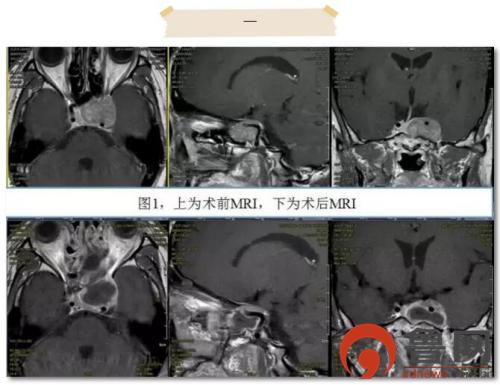

患者1为44岁中年女性,因“经鼻蝶垂体瘤术后16个月,头部胀痛半年”入院。术前鞍区MRI显示垂体瘤复发并侵袭左侧海绵窦,左侧颈内动脉完全被肿瘤包绕。手术的主要难点为如何切除海绵窦内的肿瘤。海绵窦是侵袭性垂体瘤最常见的侵袭部位,因为海绵窦内神经血管结构复杂,手术显露及切除难度增大,术后并发症增多,历来为手术禁区。王志刚教授术前组织科内多次进行讨论,最终形成意见,可采取两种手术方案:一是选择开颅手术,采取Dolenc入路,切开海绵窦顶壁及外侧壁,显微镜下切除肿瘤;二是选择经蝶微创手术,采取扩大蝶鞍的翼腭窝入路,切开海绵窦底壁及外侧壁,内镜下切除肿瘤。最终患者及家属决定行经蝶微创手术。术中开放后组筛窦、蝶窦、上颌窦后壁,显露翼腭窝,最终充分暴露鞍底及左侧海绵窦。当打开海绵窦的底壁及外侧壁后,静脉血涌出,这时不仅要切除肿瘤,还要在“血泊”中仔细辨别并保护海绵窦内走形的颈内动脉、动眼神经、滑车神经等,手术难度可想而知,恰如刀尖上跳舞。为保证安全,最终仅颈内动脉后方的一薄层肿瘤未勉强切除(图1),术中出血仅约200ml,术后患者未出现任何神经功能的缺失。脑脊液鼻漏经腰大池引流10日后完全缓解,患者顺利出院。